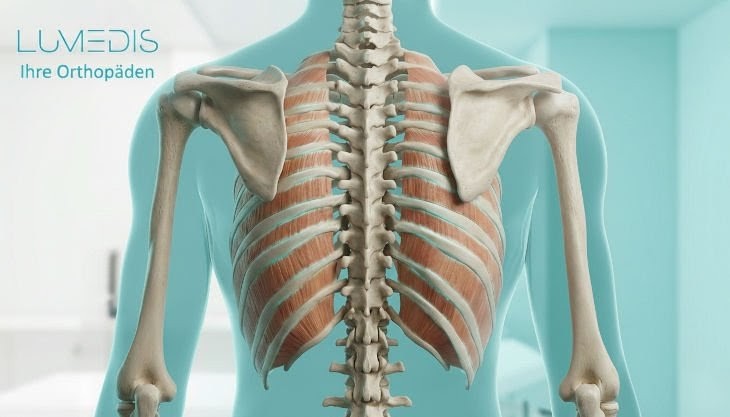

Abbildung eines Brustkorbs von hinten:

grün: Halswirbelsäule

blau: Brustwirbelsäule

rot: Lendenwirbelsäule